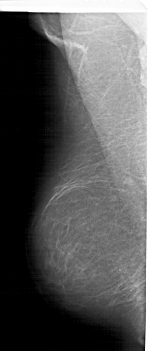

A_1422_1.RIGHT_MLO

RIGHT_MLO LINES 5971 PIXELS_PER_LINE 2971 BITS_PER_PIXEL 12 RESOLUTION 43.5 OVERLAY